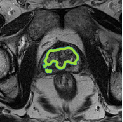

Despite their outstanding accuracy, semi-supervised segmentation methods based on deep neural networks can still yield predictions that are considered anatomically impossible by clinicians, for instance, containing holes or disconnected regions. To solve this problem, we present a Context-aware Virtual Adversarial Training (CaVAT) method for generating anatomically plausible segmentation. Unlike approaches focusing solely on accuracy, our method also considers complex topological constraints like connectivity which cannot be easily modeled in a differentiable loss function. We use adversarial training to generate examples violating the constraints, so the network can learn to avoid making such incorrect predictions on new examples, and employ the Reinforce algorithm to handle non-differentiable segmentation constraints. The proposed method offers a generic and efficient way to add any constraint on top of any segmentation network. Experiments on two clinically-relevant datasets show our method to produce segmentations that are both accurate and anatomically-plausible in terms of region connectivity.